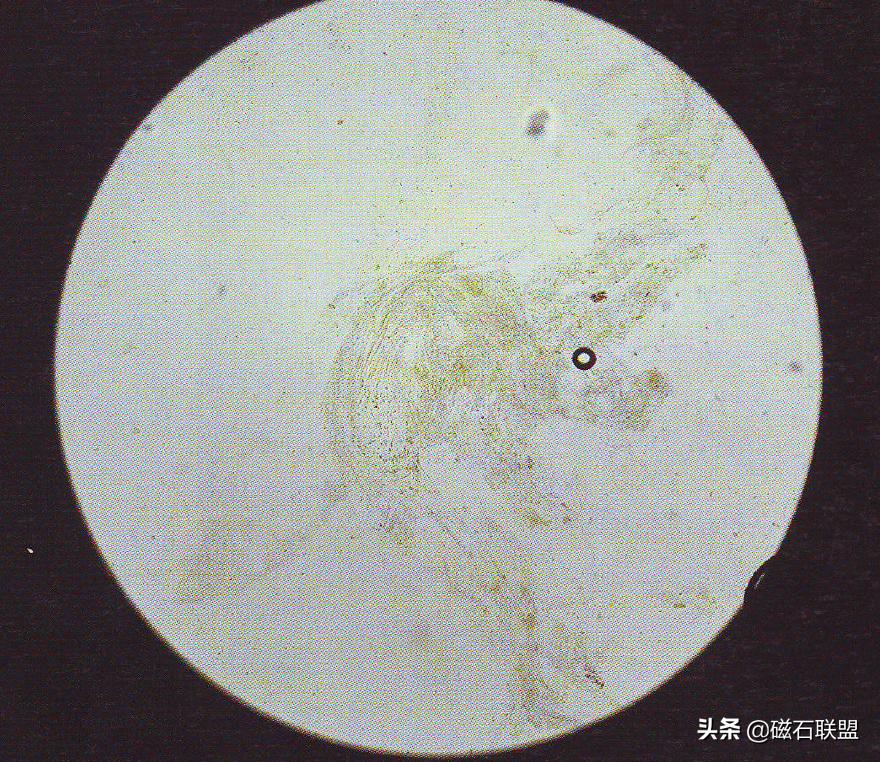

粪便检查顾名思义是采取宠物大肠末端的粪便,取上清液或者直接抹片放置显微镜下观测,主要检查消化产物、体细胞、寄生虫及肠道环境等等。

粪便检查可以让我们获得肠道内部的信息如寄生虫、肠道菌群活跃度、消化产物等等,像包括寄生虫的感染、消化不良等都可以出粪检结果中看到端倪。

本标题是全文的重要内容,一般我们到宠物医院进行粪检都是为了排查寄生虫,大部分体内寄生虫都能通过粪检检测出来,以下总结几个经常出现的情况。